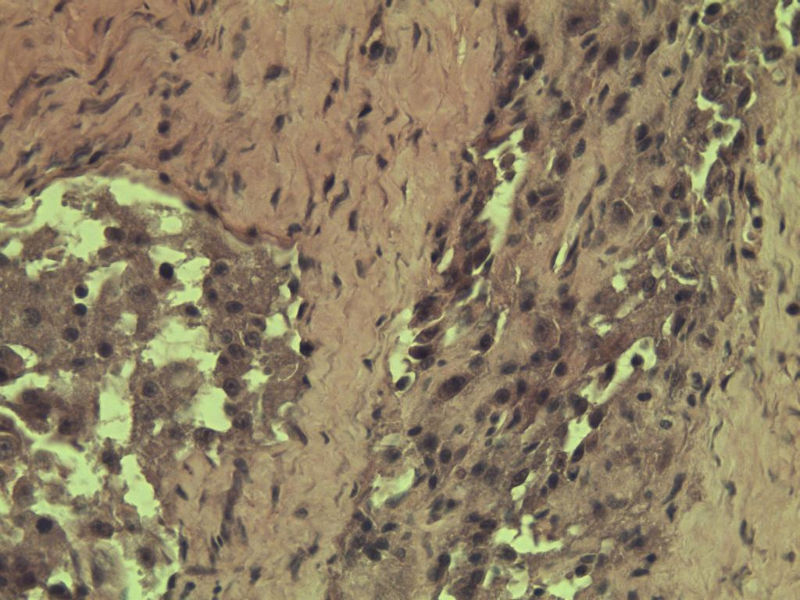

女 70岁 右颈部 头皮 多发皮下结节      取颈部部分结节送检 灰白小组织 1 块,直径 0.4 cm。 请问这个是什么?

肿瘤细胞大,上皮样,核空泡状,核仁明显,胞质嗜酸性或透明。

考虑:恶性黑色素瘤?

此片染色欠佳,取材或切面也有问题,加大了诊断的难度,恶黑确实需要考虑,但其他一些转移癌也需要排除,比如肺癌之类的,还是期待免疫组化!